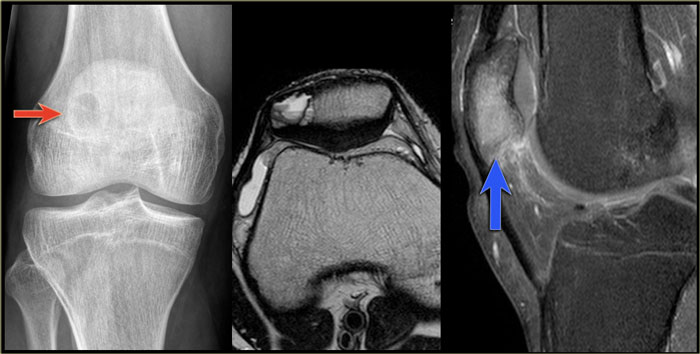

On the left more examples of GCT around the knee.

Notice that most of these lesions are well-defined and located in the epiphysis and extend into the metaphysis.

Some extend onto the articular surface (yellow arrow and small red arrows).

The lesion on the upper right has an ill-defined border with a broad zone of transition (blue arrow).

Here another typical giant cell tumor presenting as an osteolytic lesion in the epi- and metaphysis of the proximal tibia.

Non-specific intermediate signal intensity on T1WI and mixed high and low SI on T2WI with FS.

The low signal on T2WI is usually due to hemosiderin within the GCT.